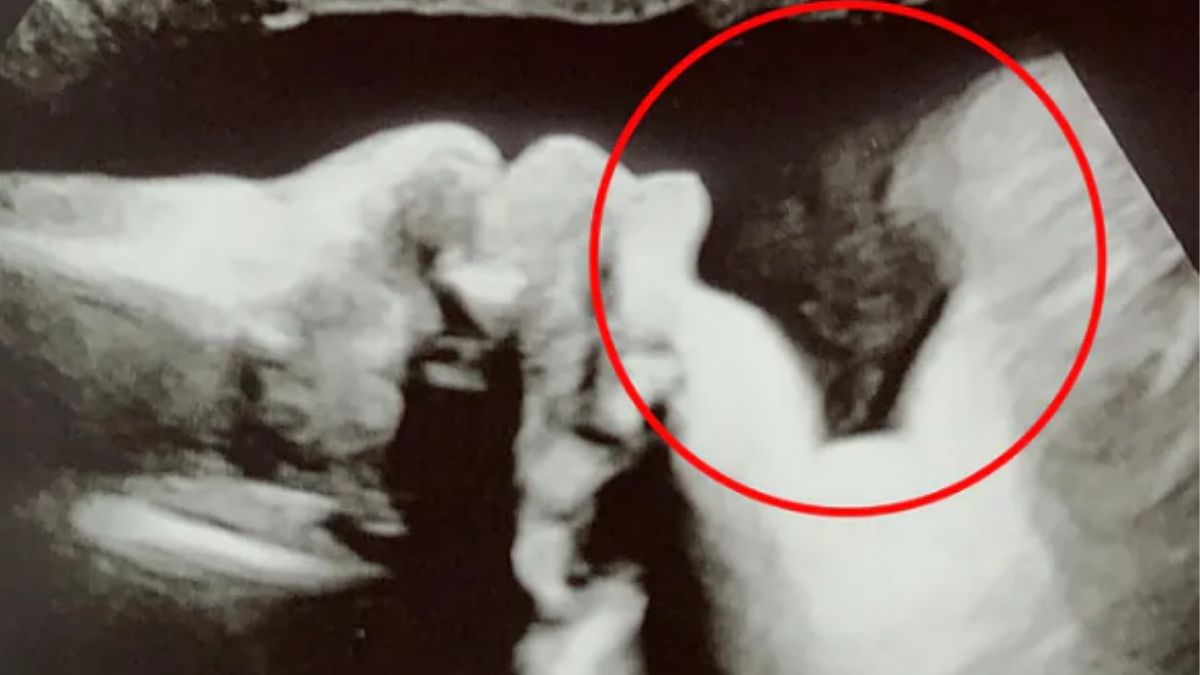

Jade Sinfield, mama dwóch pięknych dziewczynek z Londynu, oczekuje na trzecie dziecko. Niestety, dwoje dzieci straciła. Jak uważa, kolejne dziecko, które znajduje się obecnie w jej brzuchu, nie jest samo! Na dowód pokazała szokujące dla wielu zdjęcie USG. Czy to anioł?

Jak się okazało - dziecko jest zdrowe i ciąża ma swój odpowiedni przebieg, jednak to, co wstrząsnęło lekarzem to postać, którą zobaczył. Pokazał także matce, która od dziś jest pewna.

Jade twierdzi, że na zdjęciu widać anioła.

Kiedy pierwszy raz to zobaczyłam, byłam zszokowana i przestraszona, ale po pewnym czasie poczułam ulgę. Tak jakby ktoś czuwał nad dzieckiem. Po prostu jego Anioł Stróż - twierdzi Jade.

Niektórzy internauci są przekonani, że matka ma rację. Jednak większość twierdzi, że to oczywiście tylko złudzenie. A Wy? Jak myślicie?